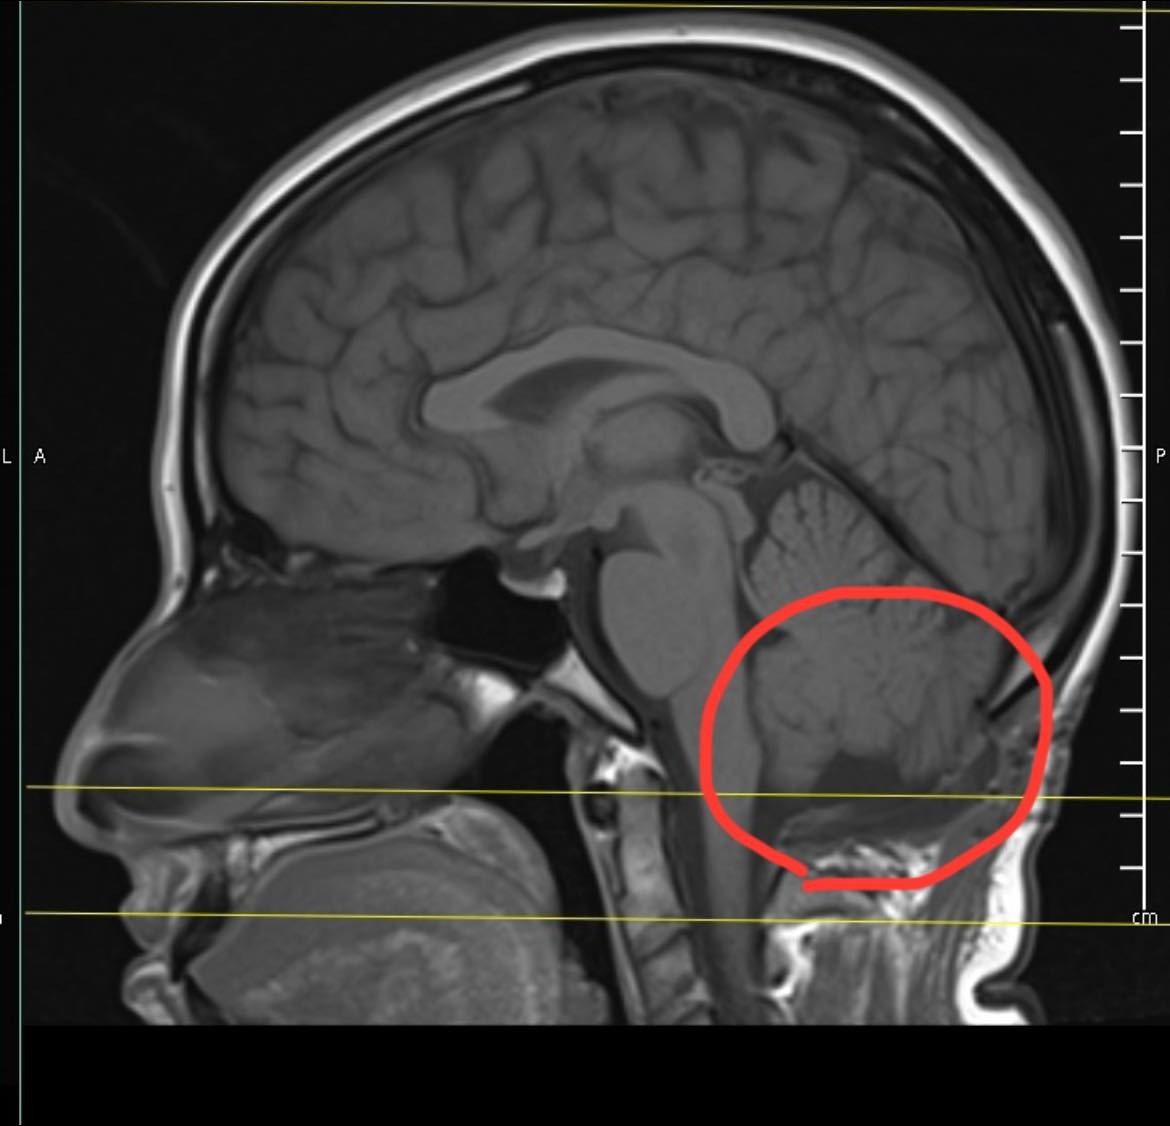

My name is Alicia, and I’m humbly reaching out as I prepare for a crucial medical journey to the Institute for Chiari & Syringomyelia in Barcelona, Spain. I’ve battled a complex neurological condition known as Chiari malformation—a diagnosis that changed the course of my life before I even turned 30.

In April 2023, I underwent decompression brain surgery in the U.S. to relieve severe symptoms including mobility loss, dizziness, and intense neurological pain. While this operation offered temporary relief, my health has since deteriorated. In the fall of 2024, I was hospitalized for small fiber neuropathy—an incredibly painful condition that left me unable to walk. These setbacks have deeply affected my independence, energy, and quality of life.

After comprehensive evaluations and scan reviews with specialists in Barcelona, I was approved for surgery in November 2025. Their team identified early signs of ischemia edema, a fluid buildup in my spinal cord that may progress into syringomyelia—cyst formations that, if left untreated, could result in permanent loss of mobility. Fortunately, we’ve caught this early.